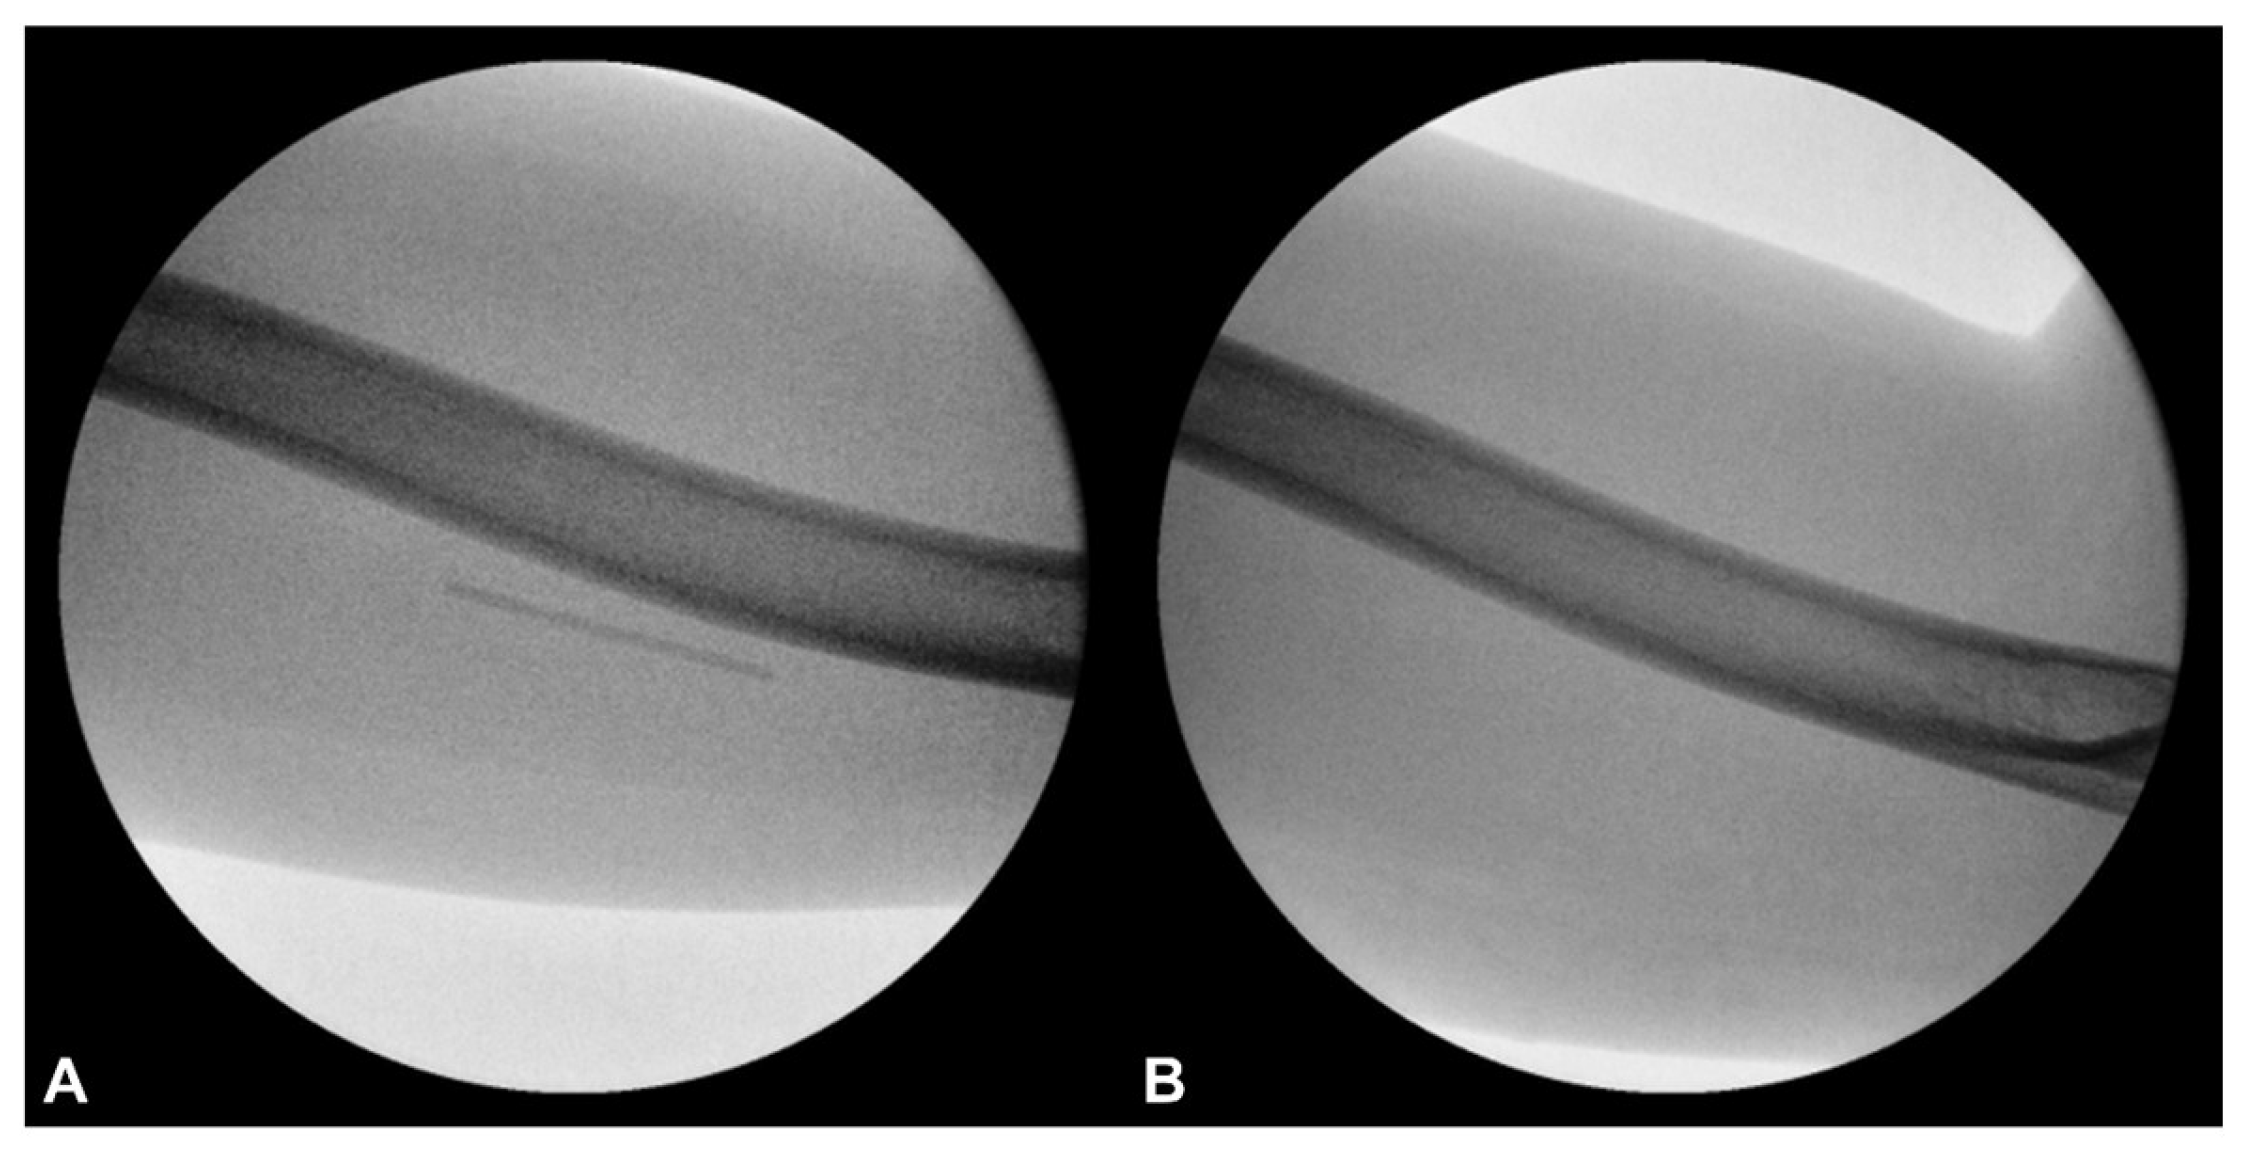

2.2. The Procedure